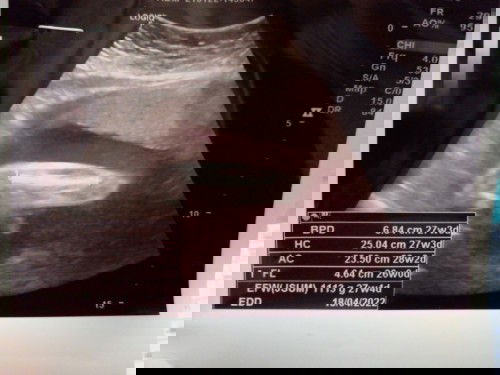

แม่ช่วยดูให้หน่อยค่ะ น้องมีจู๋ใช่ไหมค่ะ

แม่ช่วยดูให้หน่อยนะคะว่า น้องมีจู๋หรือแคม เมื่อวานอัลตร้าซาวด์มาแล้วคุณหมอไม่ยอมบอกอะไรเลยค่ะ แม่แอบลุ้นให้เป็นชาย พอดีมีลูกสาว2คนแล้ว #ขอบคุณสำหรับคำตอบค่ะ #คุณแม่ๆช่วยแนะนำหน่อยค่ะ #ขอบคุณล่วงหน้านะคะ